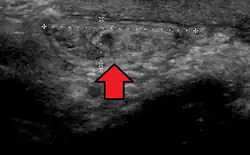

In the diagnosis of abdominal hernias, imaging is the principal means of detecting internal diaphragmatic and other nonpalpable or unsuspected hernias. Multidetector CT (MDCT) can show with precision the anatomic site of the hernia sac, the contents of the sac, and any complications. MDCT also offers clear detail of the abdominal wall allowing wall hernias to be identified accurately.[19]